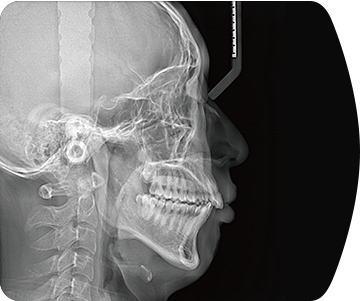

标配专业正畸软件

支持自动描点功能

精准定位

真人正侧位投影,实现CT成像区域无极可调

临床样片